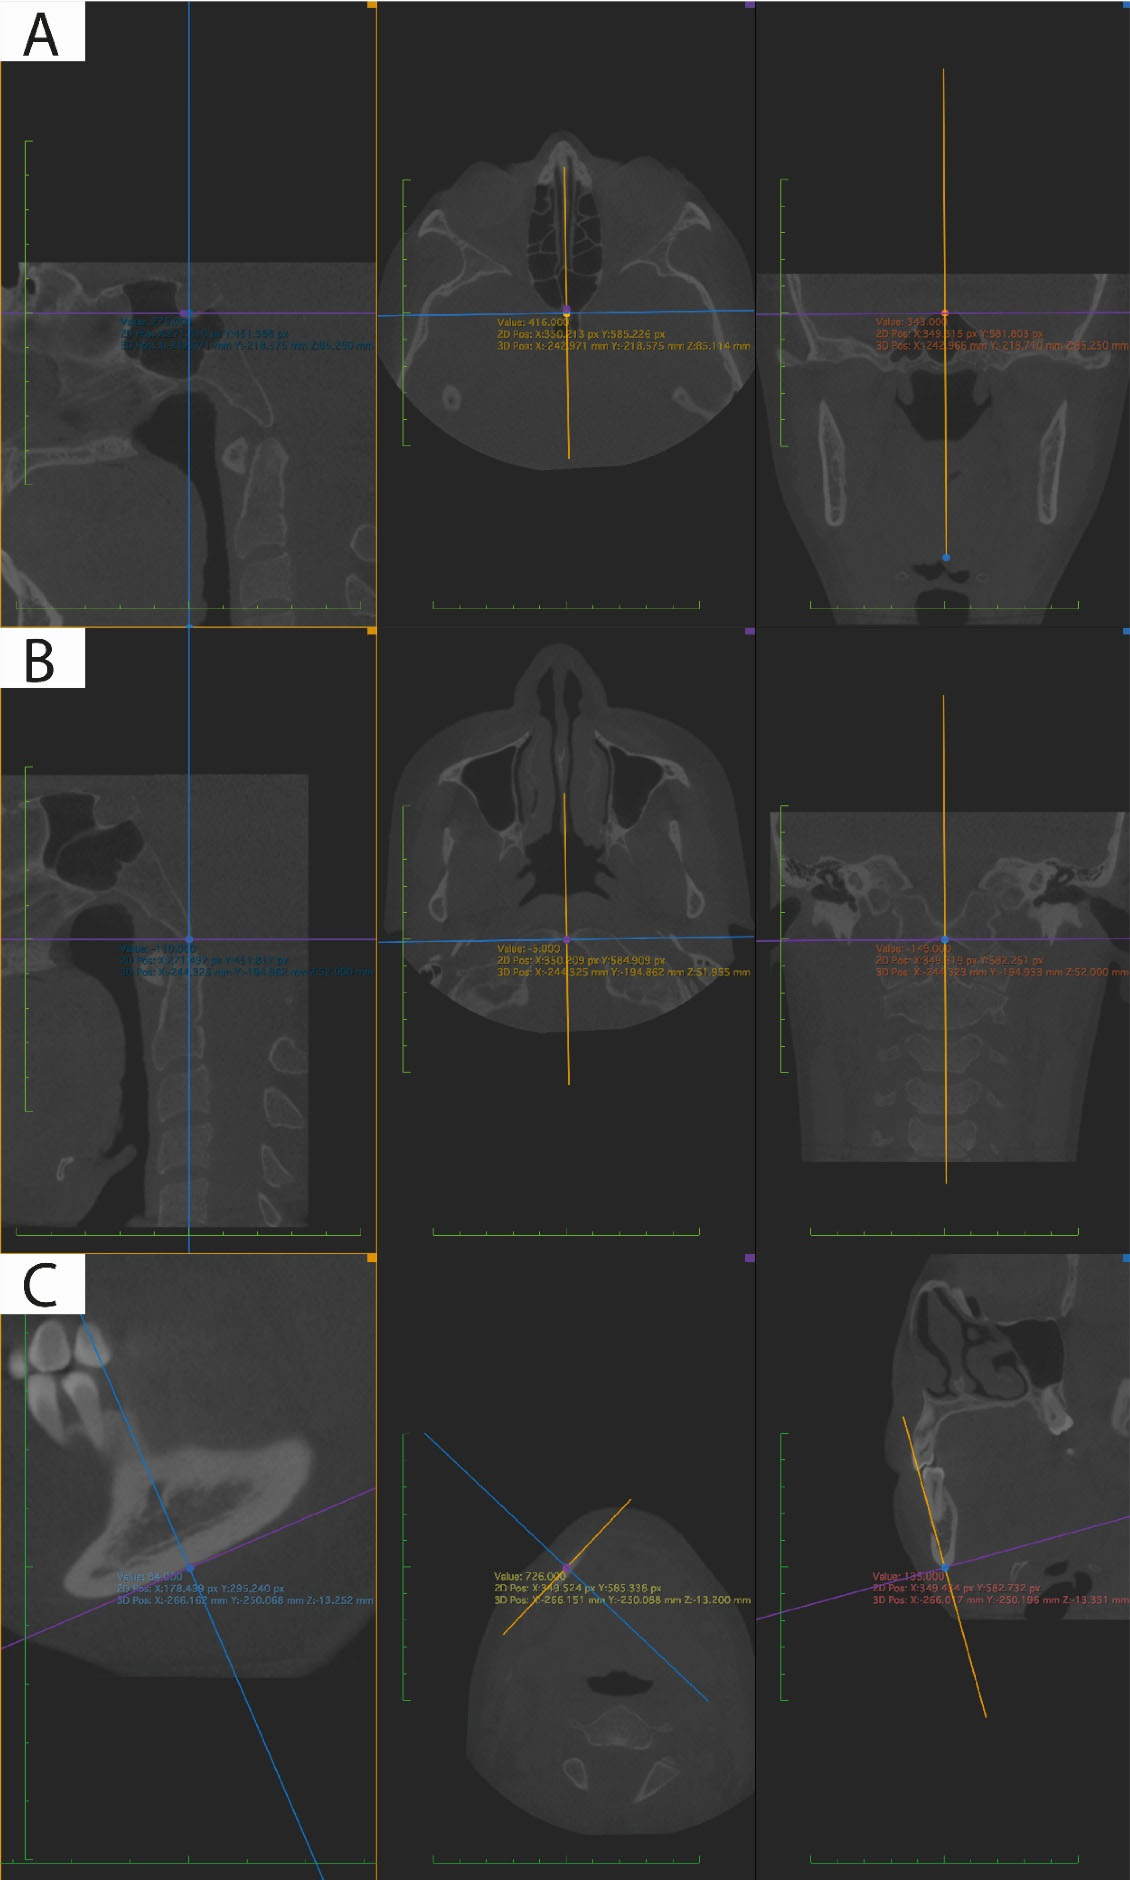

Tomographies were exported in DICOM files for viewing in Horos software (version 4.0.0; The Horos Project & OsiriX Team) in multiplanar 3D mode (MPR). The marking of each point was verified three dimensionally (Tables 1-3). The point was represented in the three windows of the spatial planes x, y, and z, each observer collected the information on the coordinates of the reference points employing image captures to record the information in tables of Microsoft Excel for Mac version 16.52 (Figure 1).

Figure 1.

Reference points marked in the multiplanar view taking into consideration the three planes of space (sagittal, axial, and coronal). A. Sella point, B. Basion point, C. Mandibular base point

Three observers were involved, two of them were orthodontists, and one was a dental radiologist. 31 reference points were chosen, and these were reviewed in two meetings in which pilot tests were carried out to describe them three-dimensionally, considering anatomical and technological criteria. A consensus was sought among the three observers that the landmarks were clearly described. These 31 reference points were marked in the multiplanar view in triplicate by each of the observers individually.